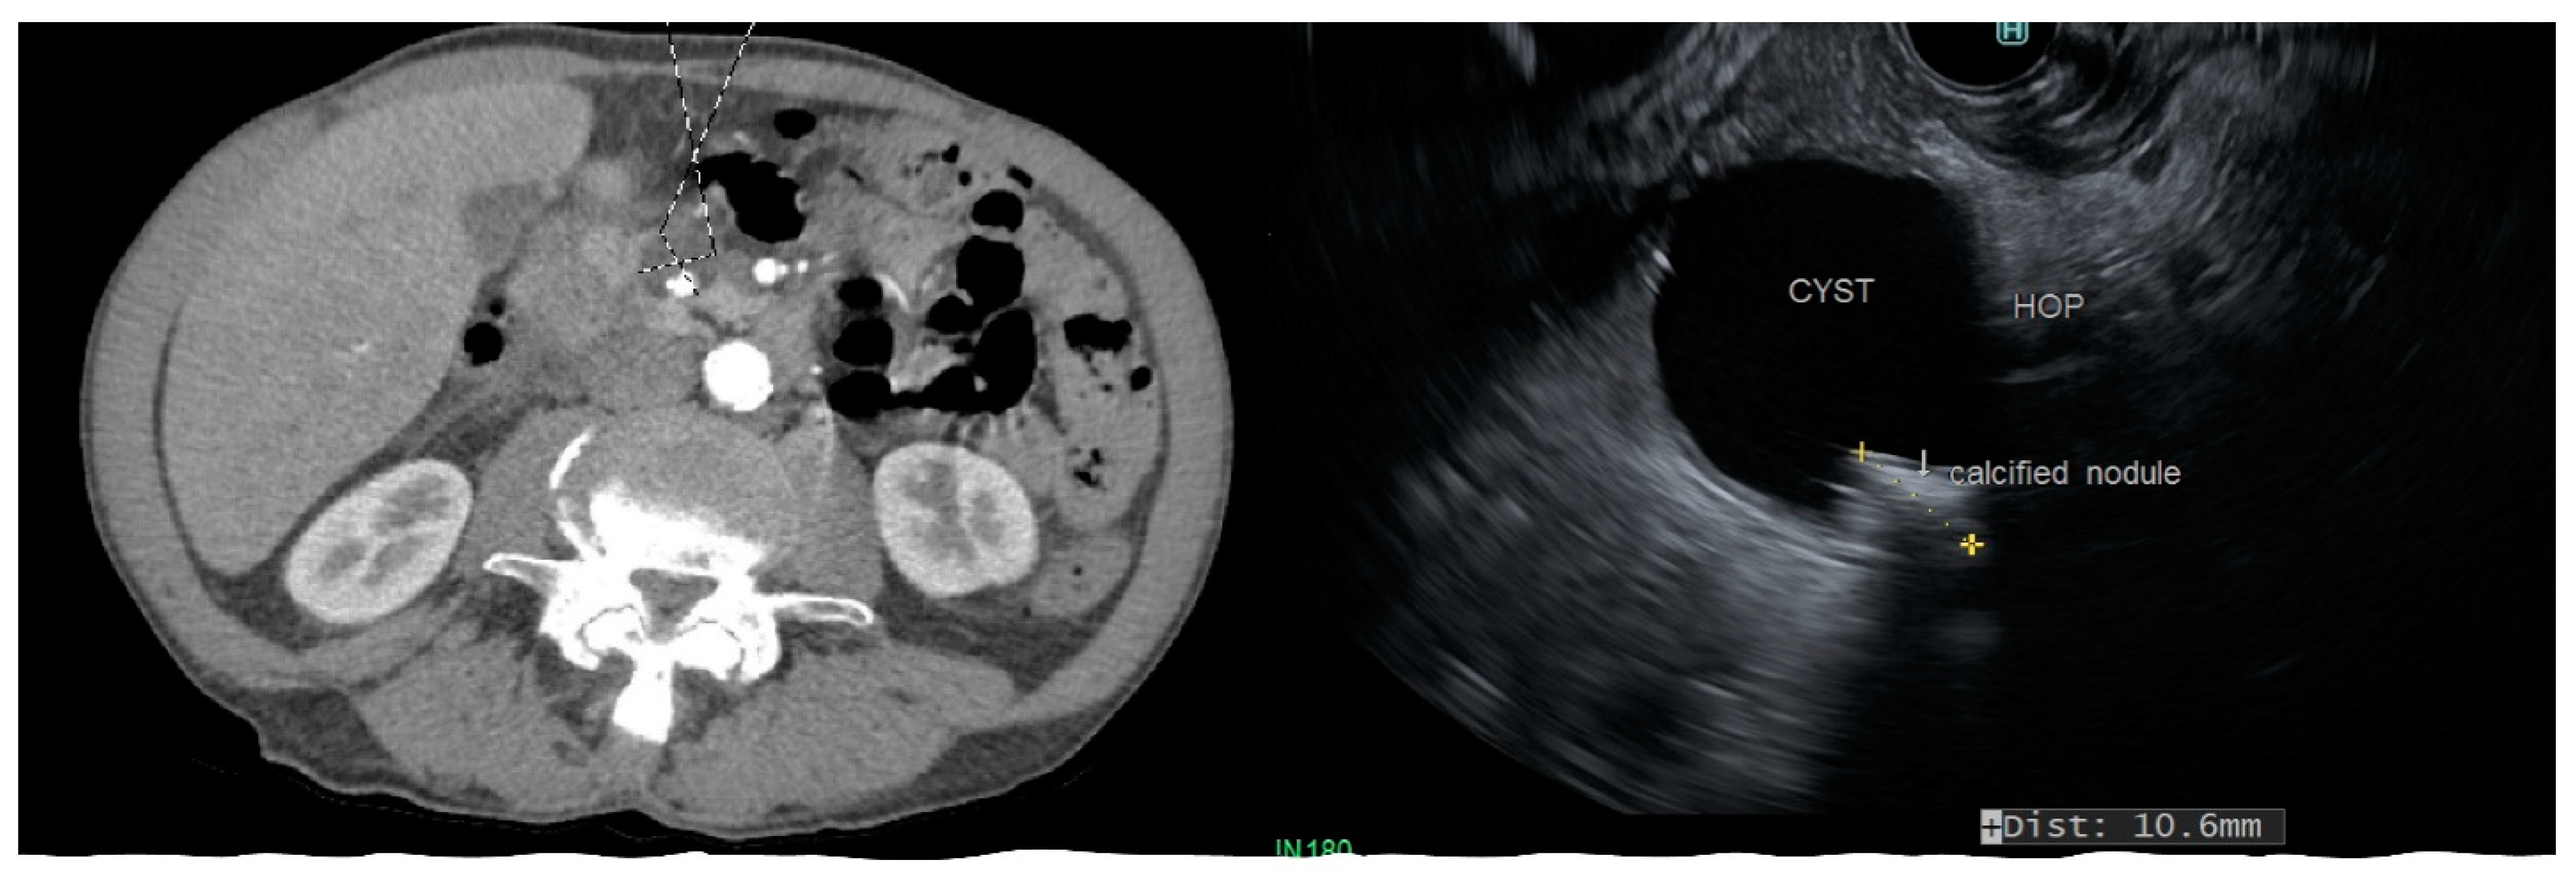

Figure 2.

CT scan and endoscopic ultrasound demonstrating a side-branch IPMN involving the head of pancreas (HOP) with a calcified mural nodule.

MCN, SCA, and SPN are solitary cysts. MCN and SCA lack communication with the main pancreatic duct and do not show pancreatic duct dilation on imaging. IPMN, by definition, demonstrate communication with the pancreatic duct, have the dilation of the duct, and are commonly multiple. IPMNs are more common in the head and neck region but can be found in other locations (Figure 2). They can be multifocal and should be considered along with pseudocysts when multiple cysts occur in the pancreas. MCNs are exclusively seen in the body or tail of the pancreas (Figure 3). While SCA can occur in the head, most SCA are located in the body or tail (~70–75%). There is no specific location of SPN (Table 1).

IPMN: The distribution of cysts in relation to the main pancreatic duct determines the malignant behavior of IPMN. Consequently, IPMN are classified as the main-duct IPMN (MD-IPMN) when MPD is dilated due to the direct involvement for more than 5 mm without a visible cyst, branch-duct IPMN (BD-IPMN), when there is a cyst, >5 mm without dilated MPD, and mixed-type when there is one or more PC > 5 mm along with the involvement of MPD. MD-IPMN and mixed-type IPMN have a higher risk of harboring invasive adenocarcinoma (approximately 45%) and high-grade dysplasia (approximately 60%), while BD-IPMN are at lower risk (16–20%) [11]. Moreover, the rate of cyst growth on follow-up can predict the risk of malignant behavior in BD-IPMN [12]. MPD dilation >10 mm in MD-IPMN, with a cyst diameter >40 mm in BD-IPMN, and the presence of a large mural nodule on EUS favor malignancy (Figure 2) [13]. Pergolini et al. followed up patients with BD-IPMN for over 10 years and found that the risk of malignancy was significant (approximately 8%) for cysts > 1.5 cm even after the five years of suggested surveillance period [14].

CT and MRI have a comparable sensitivity at differentiating malignant from benign PC, and both have equivalent accuracy at making a specific diagnosis (50–60%); however, the rate of misdiagnosis is remarkable with either imaging modality (>50%) [25,26,27]. MRI is considered better than CT at evaluating cyst morphology. Consequently, the major advantages of MRI and MRCP over CT scans are characterizing the aggressiveness of small cysts and detecting high-risk morphologic features, such as the mural nodule, septal thickening, and cyst communication with MPD (Figure 2).